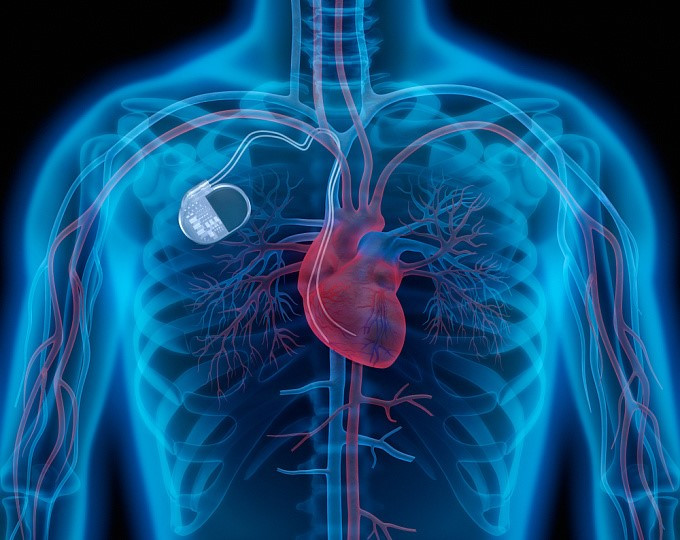

Операция по имплантации автоматического дефибриллятора-кардиовертера (АДК) является способом вернуть здоровье людям с тяжелыми нарушениями сердечного ритма. Тысячи пациентов со всего мира благодарны за новую жизнь компании Turmeda CLINICS. Под этим названием подразумевается малоинвазивная (с минимальными травмами) операция по установке специального прибора для нормализации работы сердца – автоматического дефибриллятора-кардиовертера. Обычно операция длится не более 1,5 часов. АДК представляет собой небольшое устройство, распознающее опасные нарушения сердечного ритма и нормализирующее его – проводящее антиаритмическую терапию. Последняя подразумевает создание электрических импульсов и их подачу к проводящим путям сердца. При этом пациент не чувствует боли. Если же сердце работает ритмично, то аппарат находится в режиме мониторинга и не генерирует импульсов. По показаниям пациенту могут установить одно-, двух- или трехкамерный прибор. Количество камер зависит от того, на сколько отделов сердца нужно посылать импульсы.

Что собой представляет аппарат

Размер АКД сопоставим с размерами спичечного коробка. Благодаря такой компактности прибор не сковывает движений и не ощущается пациентом.

АДК состоит из титанового корпуса, в который помещены основные компоненты устройства:

• батарея – источник питания аппарата. При его истощении требуется замена АДК. Батарея рассчитана на 3–7 лет работы прибора;

• микрокомпьютер. Он считывает данные о работе сердца, анализирует их и при необходимости трансформирует энергию аккумулятора в электрические импульсы;

• микрокомпьютер определяет мощность и продолжительность импульсов в зависимости от типа нарушения работы сердца;

• коннекторный блок. Находится в верхней части аппарата, покрыт прозрачным пластиковым колпаком. Коннекторный блок соединяет сам АДК и электроды;

• электроды. Представляют собой изолированные гибкие проводники, по которым электрический импульс, создаваемый АДК, достигает нужного отдела сердца. Количество зависит от типа аппарата.

Контроль и настройка работы АДК осуществляется врачом с помощью специального компьютера – программатора.